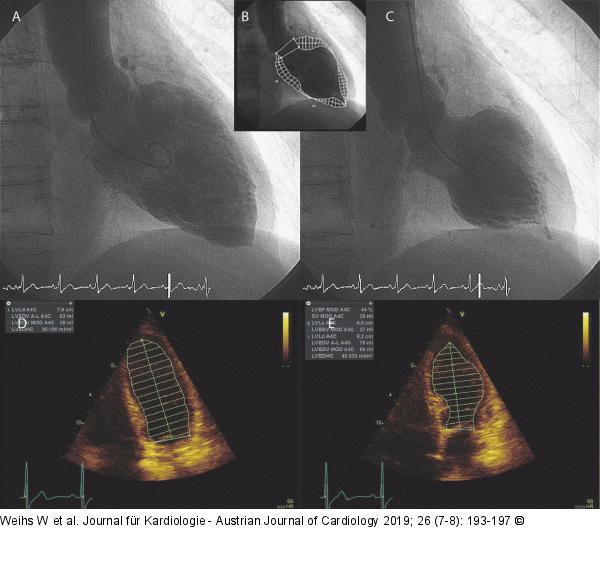

Abbildung 5A-E: Laevokardiogramm - Echokardiogramm (A): Laevokardiogramm enddiastolisch; (B): Konturumzeichnung; (C): Laevokardiogramm endsystolisch; (D): Echokardiogramm enddiastolisch mit Konturumzeichnung; (E): Echokardiogramm endsystolisch mit Konturumzeichnung. |